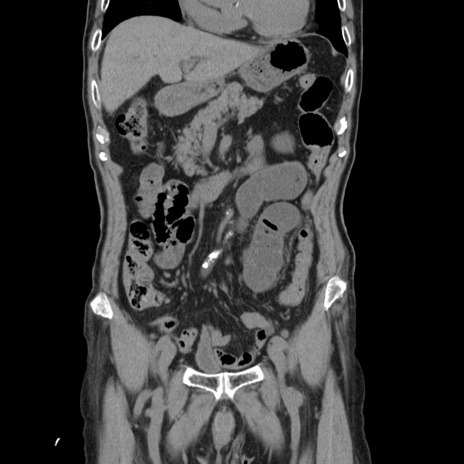

横断像

【症例】80歳代男性

【主訴】左側腹部痛、嘔吐

【現病歴】本日早朝より左腹部に痛みあり。昼頃嘔吐認めたため、救急要請。

【既往歴】直腸癌(Mile手術)、胆摘

【身体所見】意識清明、BT 35.9℃、BP 221/93mmHg、SpO2 97%(RA) 、腹部:左ストーマ周囲に限局性の腹部膨隆あり。 膨隆部自発痛・圧痛あり・軟。

【データ】WBC 7700、CRP 0.09